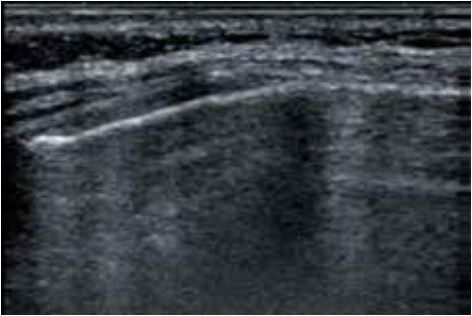

57-річна пацієнтка звернулася зі скаргами на біль у правому верхньому підребер'ї. Проте, незважаючи на численні обстеження, причину болю не було встановлено. При використанні датчика 7 МГц (PLT-704SBT, Aplio 500) (мал. 2а) структура ребер виглядала нормальною. Однак датчик надвисокої частоти виявив невеликий перелом ребра (рис. 2б), який потім був ідентифікований як причина болю. Ці невеликі переломи не могли бути діагностовані іншими методами візуалізації, що підкреслює чіткість і деталізацію, які забезпечує PLI-2004BX.

a) PLT-704SBT (Aplio 500)

б) PLI-2004BX (Aplio i-серії)

Малюнок 2. Зображення перелому ребер, отримані за допомогою PLT-704SBT (7 МГц) (а) та PLI-2004BX (24 МГц) (б).